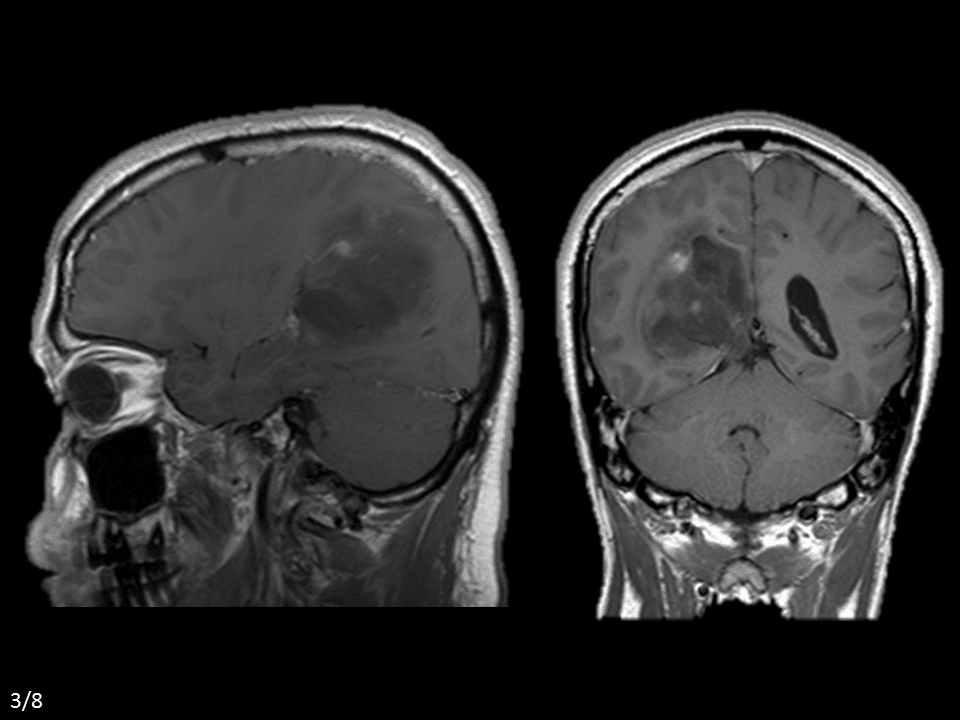

U tế bào hình sao

» Thông tin: Nam giới – 42 tuổi.

» Lâm sàng: Đau đầu.

# U sao bào kém biệt hóa (Anaplastic Astrocytoma)